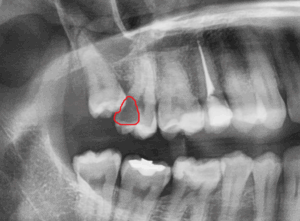

Weisheitszahn begünstigt die Kariesbildung an Nachbarzähnen – Auf dem ersten Bild ist ein Weisheitszahn (schwarzer Pfeil) abgebildet. Dieser ist nur teilweise durch die Schleimhaut durchgebrochen und erschwert die Zahnreinigung am Nachbarzahn. In der Folge hat sich an diesem Zahn eine große Karies gebildet. Die Karies ist zum besseren Verständnis auf dem zweiten Bild durch eine rote Umrandung hervorgehoben. Es ist deshalb ratsam Weisheitszähne, die die Zahnreinigung erschweren, rechtzeitig zu entfernen.